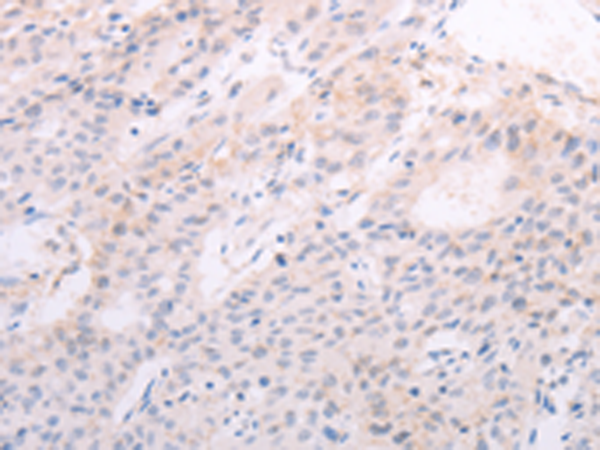

分类: 科研抗体货号: P07679别名: RNF84; MGC:39780应用: IHC反应种属: Human, Mouse